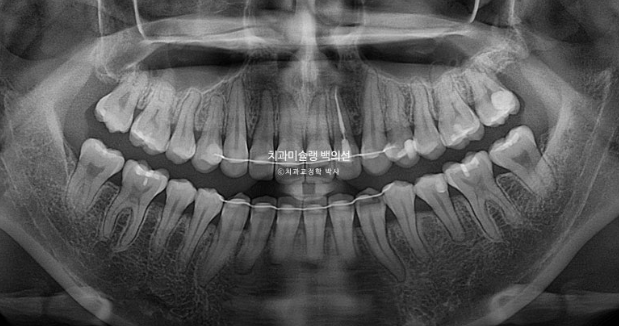

엑스레이 검사 결과 뼈의 비대칭은 경미하나 상하 치아중심선이 어긋나있어서 이 부분 개선을 원하셨습니다.

위 앞니 기준 약 2mm 합입이 되었습니다.

위 어금니도 마찬가지로 약 2mm 합입이 되었습니다.

한마디로 상악 전체치열이 2mm 합입되었고 뒤로는 약 2mm 후방이동 하였습니다.

앞니뿐 아니라 어금니까지 상악 14개 전체치열의 후방이동 및 합입으로 아래턱이 자가회전하며 턱끝이 짧아졌습니다.

25.08

치근 평행도는 좋으며 치근흡수는 보이지 않습니다.